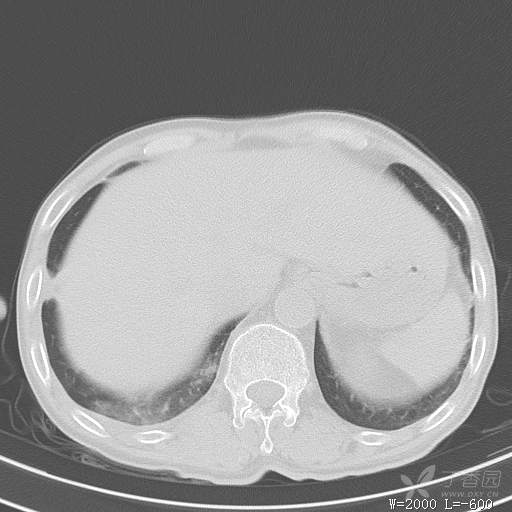

简要病史:主因发热伴腰背部疼痛2小时于2018-06-27,09:30 入院。患者无高血压,冠心病、糖尿病病史,无慢性咳喘史,不吸烟。否认食物药物过敏史。患者于入院前2小时出现发热,体温37.5℃,无咳嗽,咳痰,伴右侧腰背部疼痛,伴呕吐2次,呕吐物为黄绿色胆汁,大便2次,为稀便,无咯血,无胸闷、憋气,无鼻塞、流涕,无尿频、尿急、尿痛,就诊于我院,我院急诊查:上腹部CT:右肾结石,右下肺感染性疾病可考虑,血常规WBC13.54*109/L,GR%45.8%,急诊以“发热待查:肺感染?”收入院。

辅助检查:上腹部CT:右肾结石,右下肺感染性疾病可考虑,血常规:WBC13.54*109/L,GR%45.8%,。心肌酶示:谷草转氨酶12U/L,乳酸脱氢酶328U/L,肌酸激酶20U/L,肌酸激酶同工酶7U/L,α-羟丁酸脱氢酶277U/L,查凝血常规示:凝血酶原时间12.5秒,国际标准化比值1.07,活化部分凝血酶原时间32.6秒,纤维蛋白原浓度1.77g/L,凝血酶时间15.6秒。

临床诊断:1.腰背部疼痛原因待查:1.肺炎?2.泌尿系结石?。